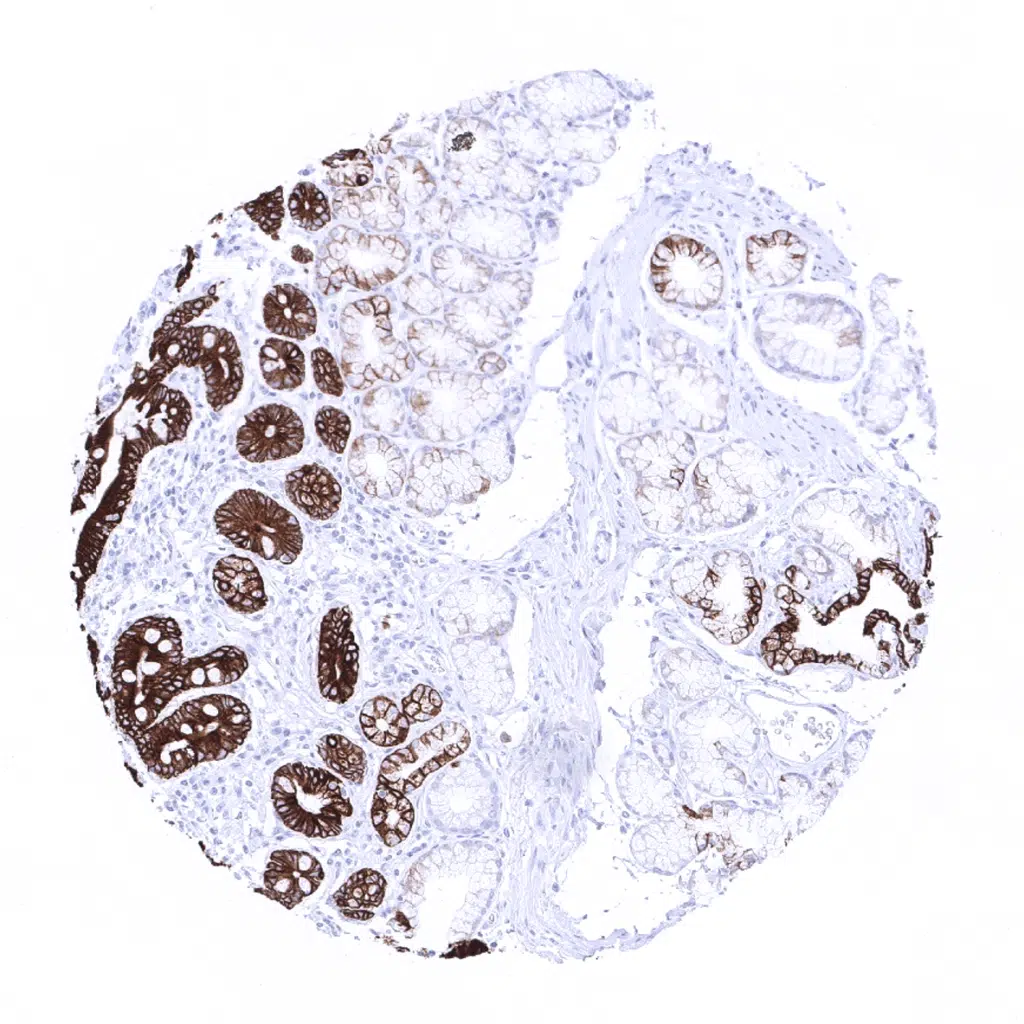

Prostate - A variable cytokeratin 19 staining intensity of both apical and basal cells can occur in the prostate but not in all glands and not in all samples.